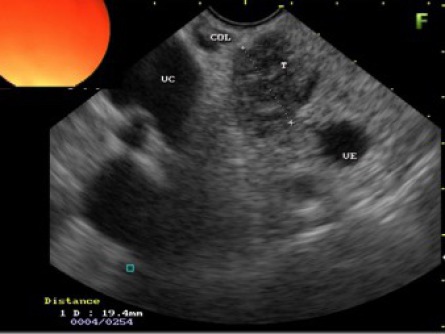

La ecoendoscopia o ultrasonografía endoscópica (USE) es una técnica que combina la endoscopia con la ecografía para conseguir cortes ecográficos desde el interior del tubo digestivo en todos los planos del espacio y en todas las localizaciones donde llega el endoscopio.

Con ello se consigue una buena visualización de las distintas capas de la pared del tubo digestivo (esófago, estómago, duodeno hasta la segunda porción y recto) y de las estructuras de vecindad (mediastino, lóbulo izquierdo hepático, bazo, páncreas, vía biliar, vesícula biliar, vasos esplénicos y mesentéricos superiores y sistema venoso portal en el tracto digestivo superior y estructuras de la región pélvica y esfínter anal en el tracto digestivo inferior).

Este examen se utiliza para evaluar una anormalidad, como una protuberancia o lesiones, detectadas en una endoscopia anterior. La ultrasonografía EUS ofrece una imagen detallada de la protuberancia o lesión, que puede ayudar al médico a determinar su naturaleza y a decidir cuál es el mejor tratamiento.